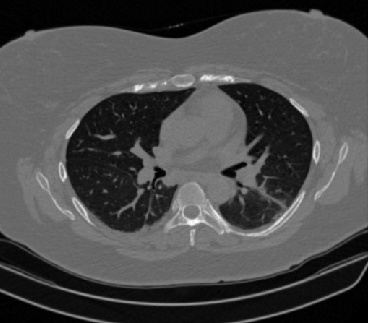

It should be mentioned that for explainability purposes [7, 8, 9], an anchor set was generated for the COV19-CT-DB database [5]. This included 11 anchors, each representing a respective 3-D CT scan obtained through an appropriate clustering procedure. Figure 2 shows a series of slices from a COVID-19 case, whereas Figure 3 shows a series of slices from a non COVID-19 case.